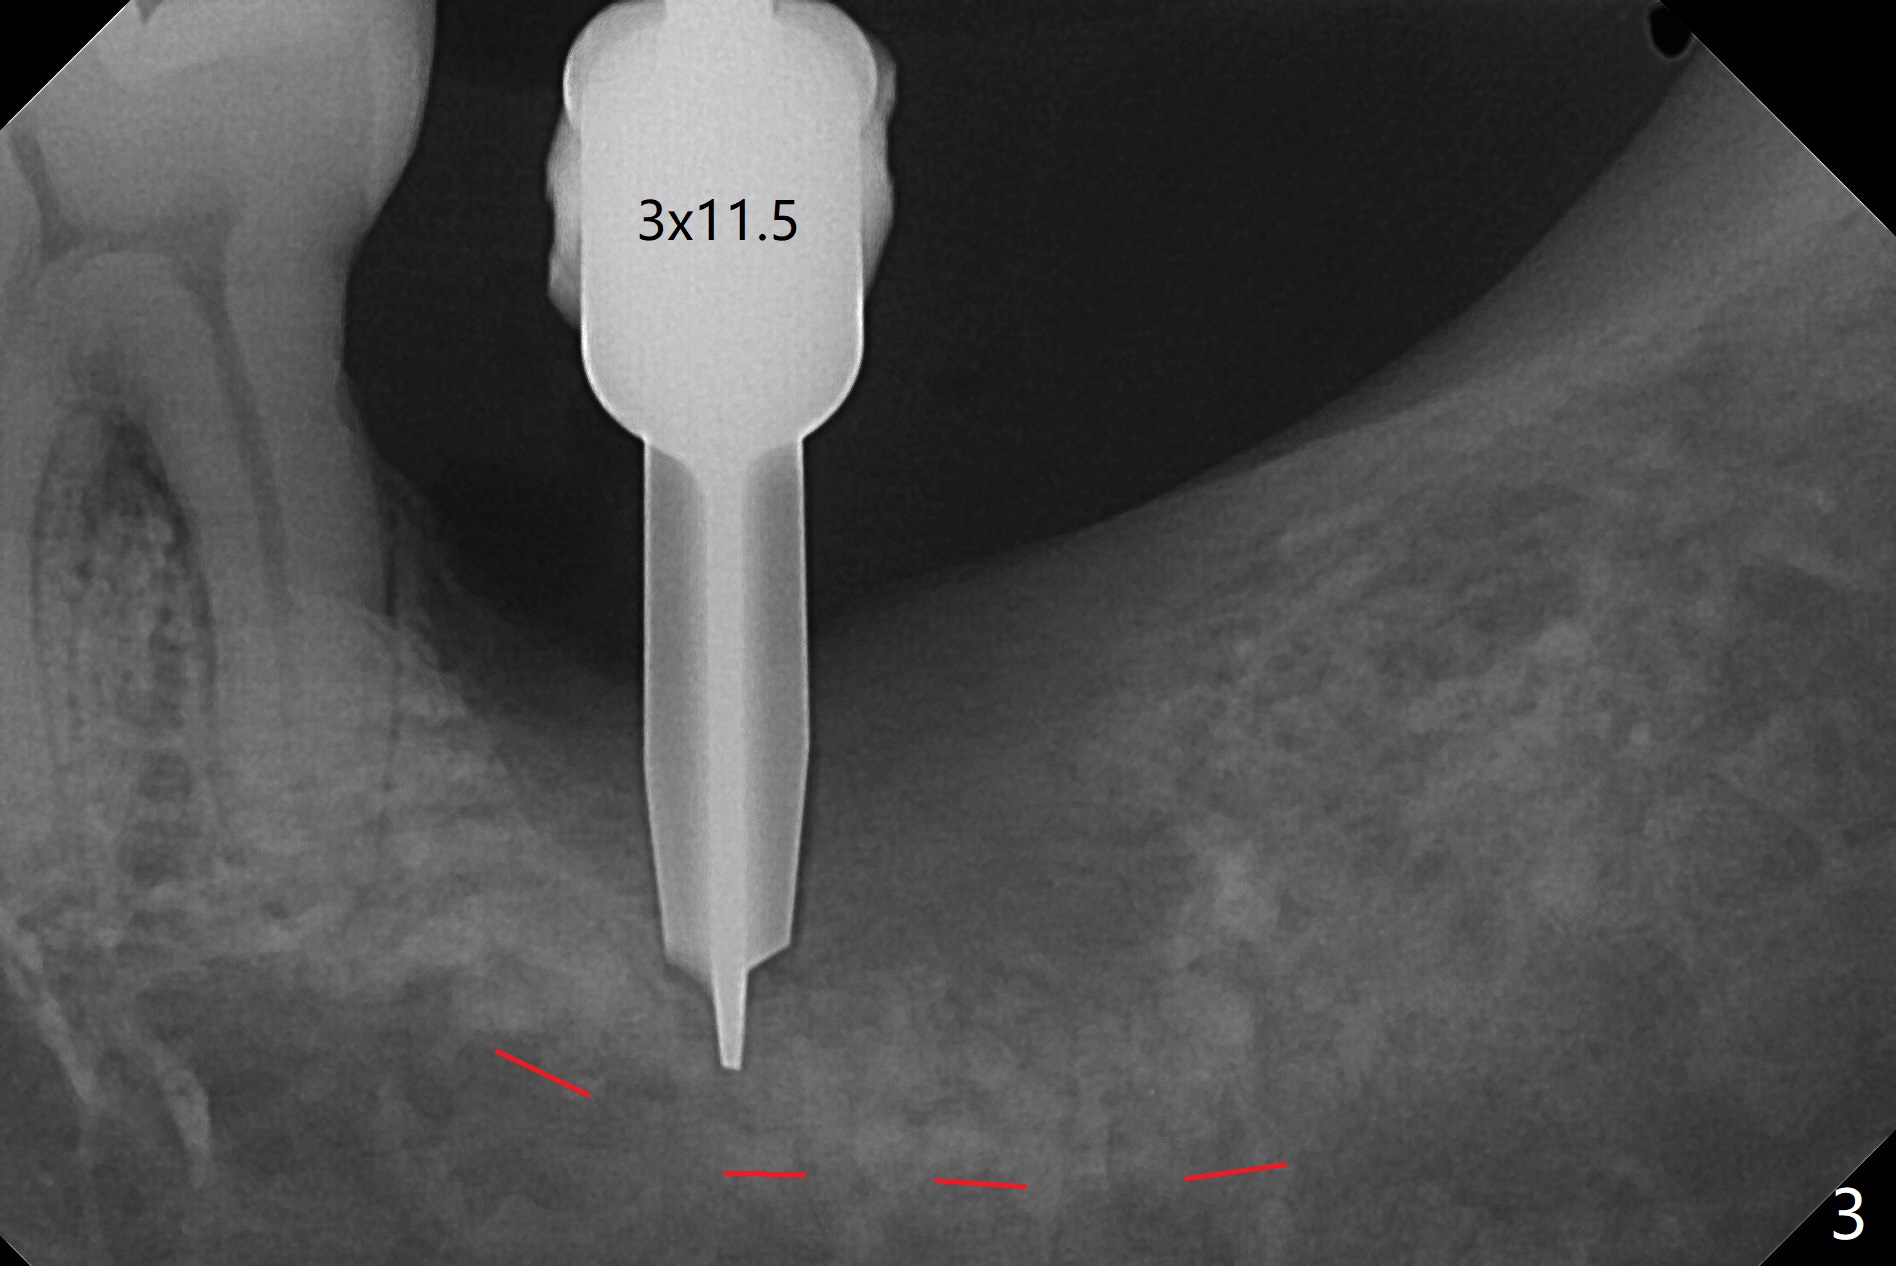

病人回来左下7拔牙植牙,十分感激导板取模后松动牙固位(图一),让他能正常吃饭。去除颊侧树脂和钢丝,6,7之间树脂自动脱落。拔牙后,肉芽组织很多,需要把局麻药注射至肉芽组织中,刮除时不慎远中舌侧牙龈穿孔。尽管纱布压迫,渗血相当多。怀疑导板就位不全,没有纠正。完成钻洞,报废植体无法就位。放置最后一个钻头,根尖片显示钻洞太浅了(图二)。再次磨除6颊侧,远中树脂,导板好像就位,重复钻洞,仍旧太浅(图三),CT表明钻洞偏颊侧(图四)。准备徒手改变钻洞,但是病人疼痛,只好植骨(粘性骨粉)(图五),牙槽窝舌侧,咬合面各覆盖一张PRF膜(图六:箭头),牙间隙维持器和牙周敷料固定。导板在曾经有树脂地方必须缓冲(图七:6;八:*,与图一对比),磨除深度有时不准确。术后两周牙周敷料仍稳定(图九),虽然病人希望撤除,我们偏向保留。反正病人正在做局部牙齿矫正。术后三周牙周敷料脱落,左上6咬合面树脂为了对侧局部牙齿矫正(图十)。骨粉有些丧失(图十一),最好手术时使用不可吸收膜。术后四个月牙槽窝充满骨粉,可以在下齿槽管颊侧植入4x8.5毫米植体(图十二)。